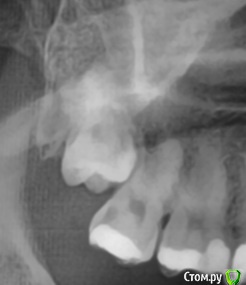

analyst Опубликовано 22 февраля, 2015 Поделиться Опубликовано 22 февраля, 2015 Приветы!Спрогнозируйте пожалуйста, можно ли удалить седьмой зуб и на его место "вытянуть" восьмой? Будет ли он так же функционален? Ссылка на комментарий

orthophil Опубликовано 22 февраля, 2015 Поделиться Опубликовано 22 февраля, 2015 (изменено) Теретически возможно. Насколько долго и сложно сказать по этому снимку нельзя. А есть ли смысл? И зачем удалять седьмой? Изменено 22 февраля, 2015 пользователем orthophil 1 Ссылка на комментарий

analyst Опубликовано 22 февраля, 2015 Автор Поделиться Опубликовано 22 февраля, 2015 (изменено) Зачем? Если речь об удалять-тянуть, то для того чтобы не чувствовать себя ущербным при пережевывании пищи. Судя по тому, что с седьмым зубом все плохо, такое чувство может скоро наступить. зачем удалять седьмой? Спасибо за ваш прогноз! Терапевт не видит положительных перспектив у этого зуба. Снимок несвежий, там скол под десну. Изменено 22 февраля, 2015 пользователем analyst Ссылка на комментарий

orthophil Опубликовано 22 февраля, 2015 Поделиться Опубликовано 22 февраля, 2015 Может все же попробовать с 7м поработать? Поговорите со своим врачом. Скол под десну сколу под десну рознь. Ссылка на комментарий